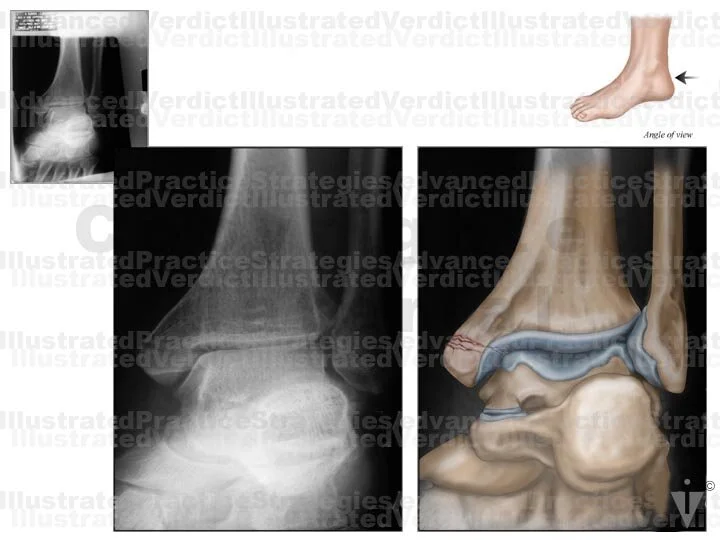

BOARD 16

1. Original film

2. Original film with enhanced illustration